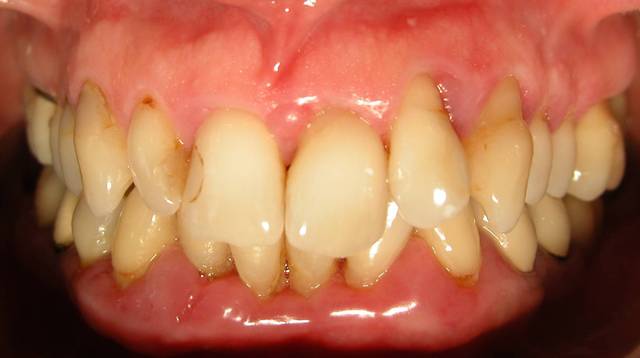

Voici le cas d'une patiente que j'ai traité pour une parodontite chronique.

Donc il s'agite d'une patient adressée par un confrère pour un avis paro avant un traitement ODf. La patiente a cinquante cinq ans. Elle fume des cigares, des problèmes d'hygiène. Je dignostique une parodntite chronique que j'ai traité en non chirurgical. La patiente est en observation avant d'entamer un traitement prothétique plutôt qu'ODF.

La consultation: DSCN 7002

1 mois après la consultation et motivation à l'hygiène: DSCN 7502

Le jour de la lithotriptie: DSCN 7030

6 mois après: DSCN 0013